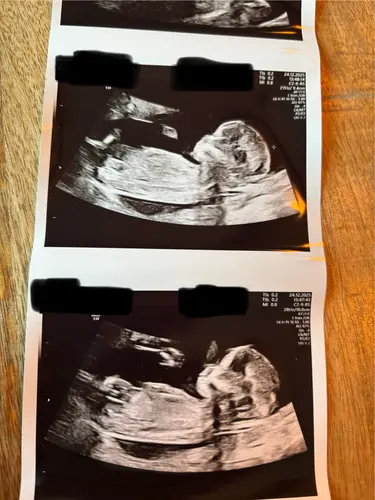

Ik had met de 13 weken echo hier een foto geplaatst waarop de Nub goed te zien was, bijna iedereen dacht dat het een meisje was waarvan een paar zelfs helemaal overtuigd. Twee personen zeiden een jongetje en wat bleek vandaag inderdaad een jongen 🤣😂😂.

Zo zie je maar de nub beoordelen zegt niet alles. We zijn hartstikke blij met een jongen overigens hoor! 😁😁